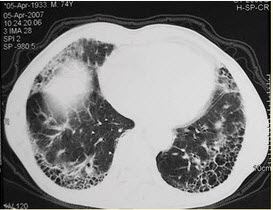

患者女,23岁。间断发热伴皮疹1年半,诊断红斑狼疮。长期间断应用糖皮质激素治疗。近20d来高热(T39℃)伴咳嗽咳痰,CT(附图)示双肺满布圆形密度增高阴影,大小不等,密度不均匀,上、中肺野分布较多,双侧少量胸腔积液。血常规:WBC2.52×109/L,N0.62,Hb92g/L;ESR40mm/h;痰真菌培养:烟曲霉3次阳性;支气管镜检查右下叶、左舌段见黄色黏液性血性分泌物,毛刷找到霉菌孢子。